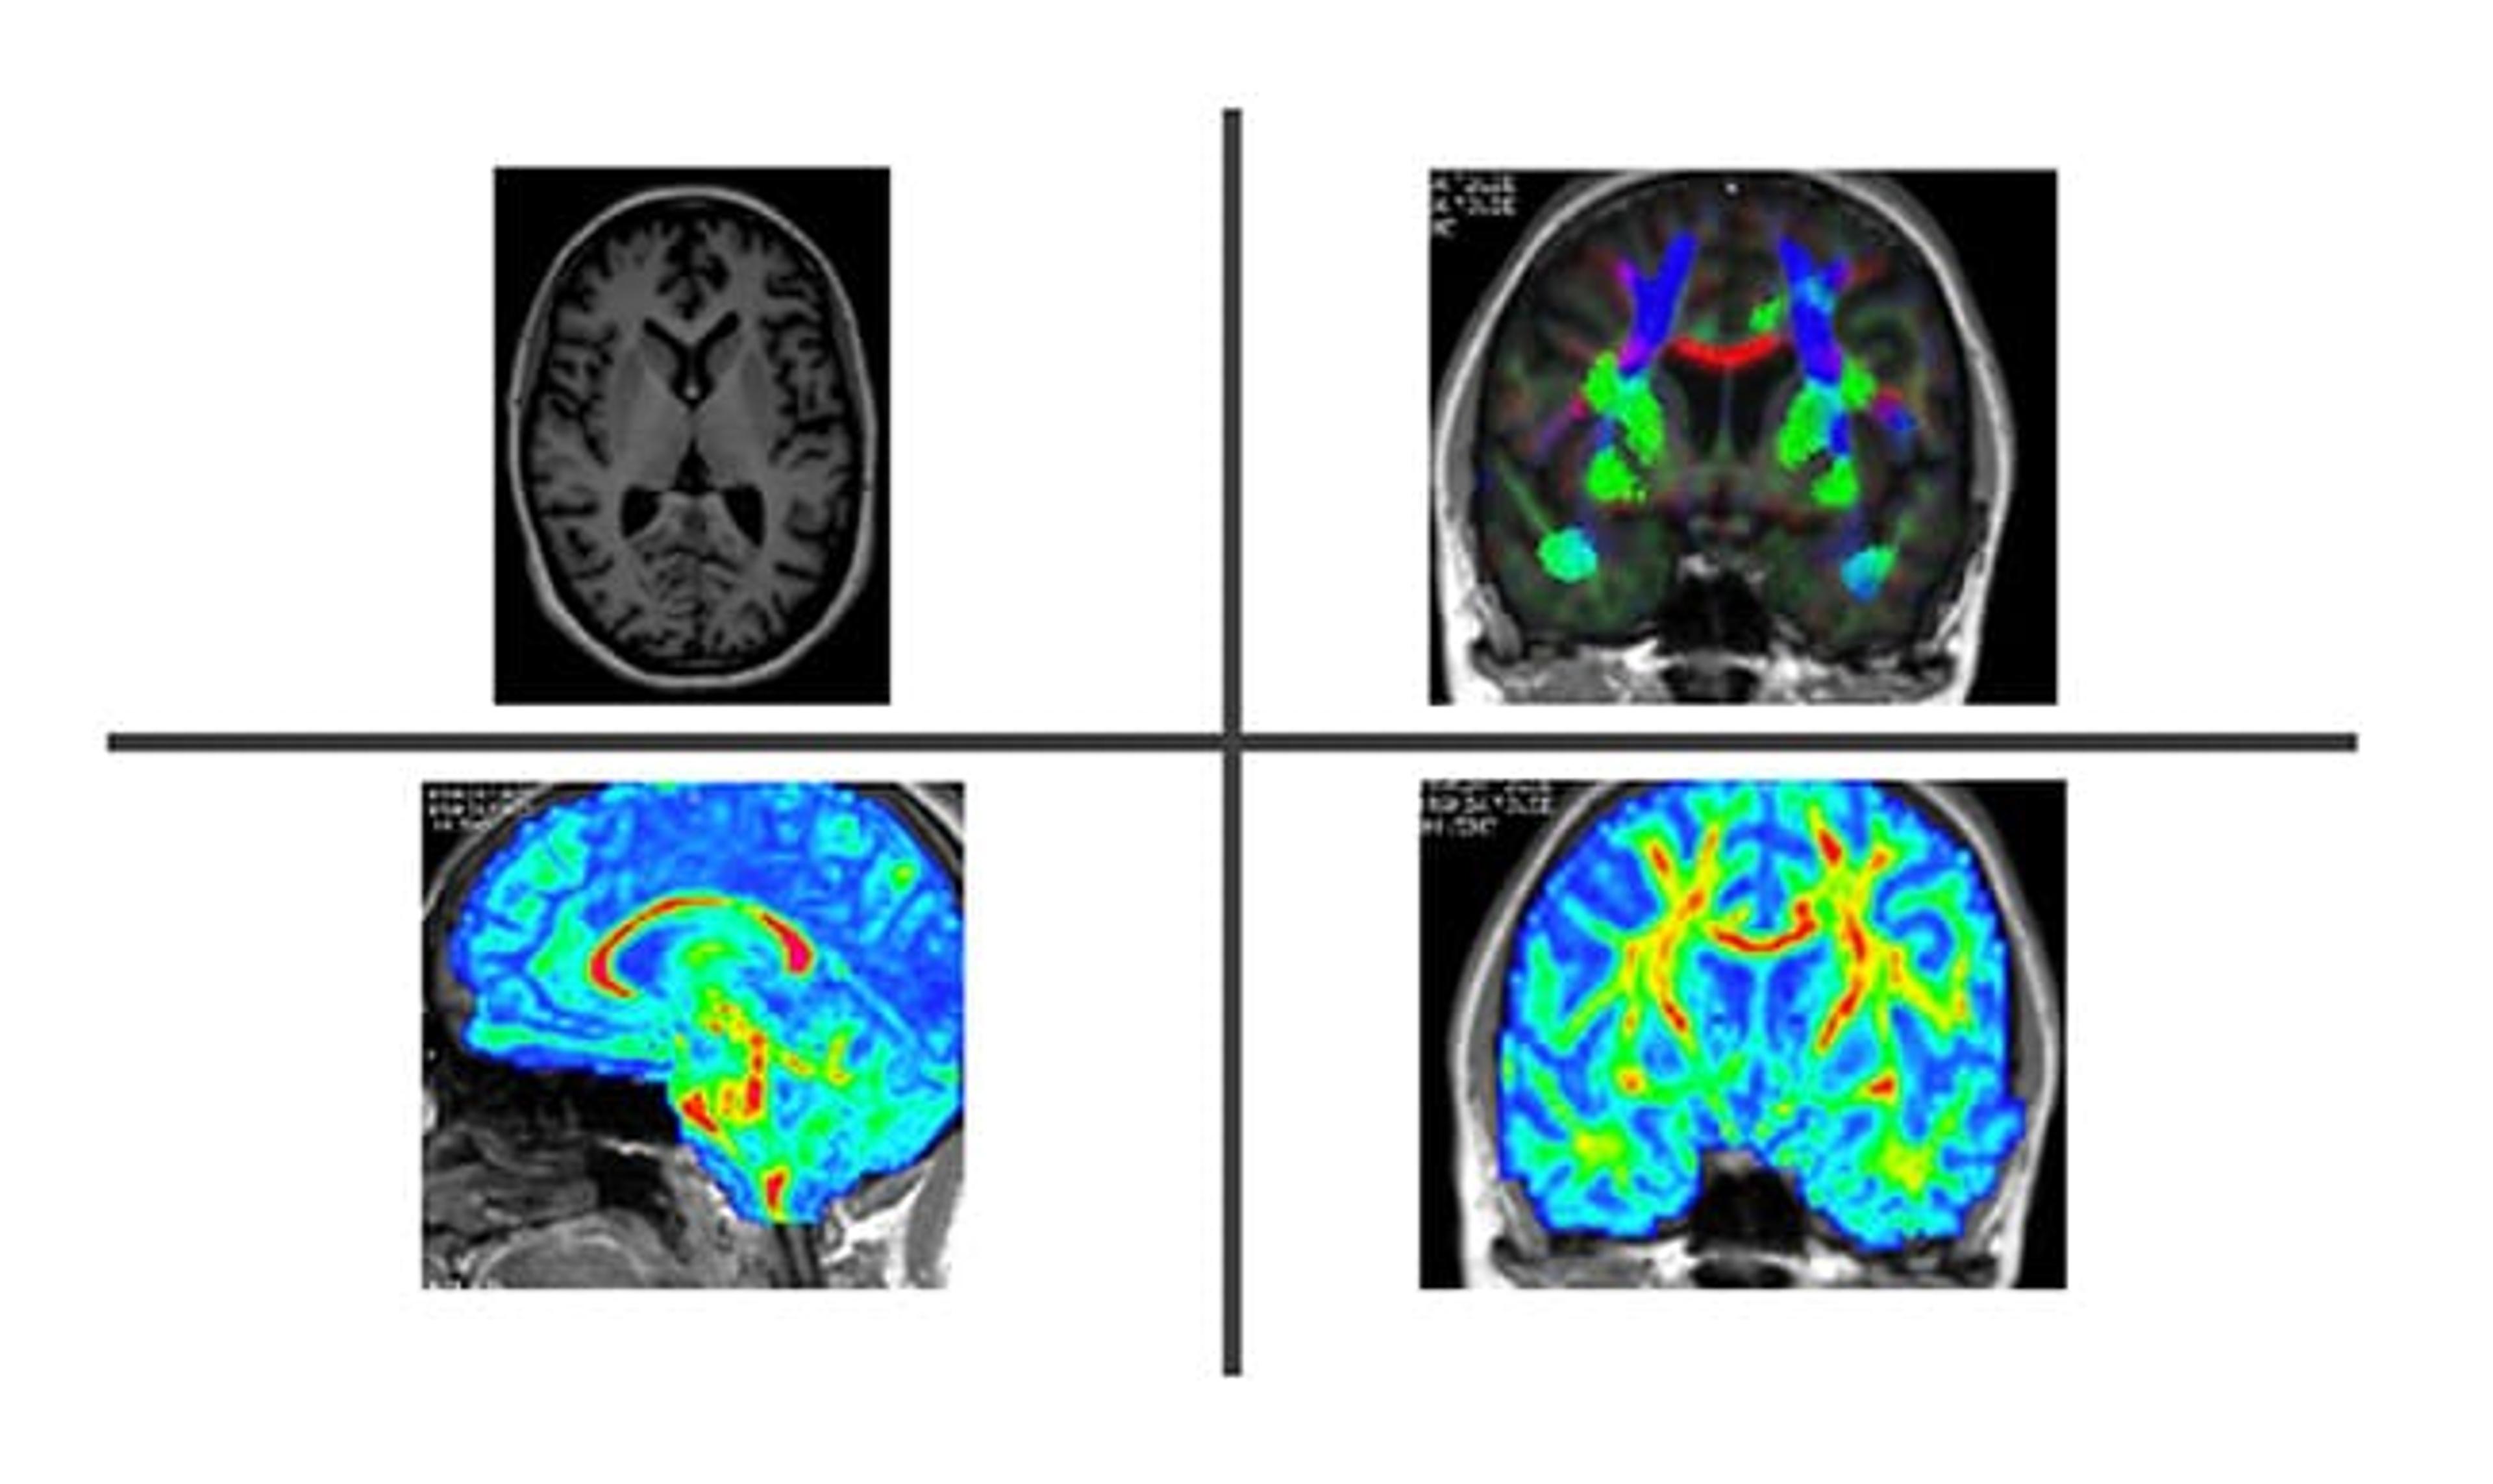

PRISM Imaging specializes in the comprehensive assessment and treatment planning of seizure disorders, utilizing pioneering imaging techniques such as:

- Seizure Focus Assessment Using DTI (Diffusion Tensor Imaging): Through the use of advanced DTI, PRISM offers in-depth evaluations to locate the seizure's focal point within the brain. This precise identification of seizure origins can inform treatment strategies and potentially improve patient outcomes.

- Quantitative Brain Mapping: PRISM's cutting-edge quantitative brain mapping aims to pinpoint specific areas of the brain involved in seizure activity. This technique can provide valuable data to better understand each patient's unique seizure disorder.

- Identifying Areas of Degeneration Causing Seizures (e.g., Mesial Temporal Sclerosis): By recognizing and examining areas of brain degeneration, such as those caused by conditions like Mesial Temporal Sclerosis, PRISM strives to enhance our understanding of the potential causes behind individual seizure disorders.